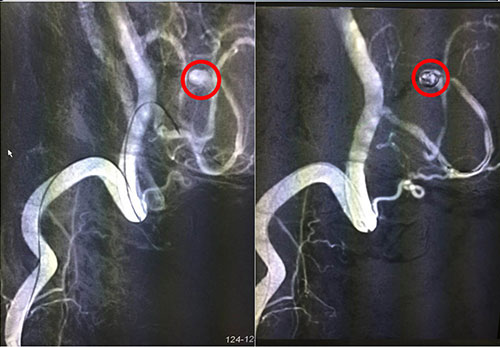

红圈内为术中介入微导管微弹簧

脑动脉瘤的介入治疗,最常用的是用弹簧圈栓塞动脉瘤。简单地说,就是从大腿根部的股动脉插管,将一根很细的微导管通过动脉官腔内直接插到脑动脉瘤内,再通过这根很细的微导管送入一段一段盘旋的微弹簧圈,逐步将动脉瘤腔内填满,诱发血栓形成后,使动脉瘤腔没有血流通过,而正常的脑动脉保留通畅,从而达到治疗的目的。12月6日手术进行,术程顺利,患者安返ICU进行术后监护。